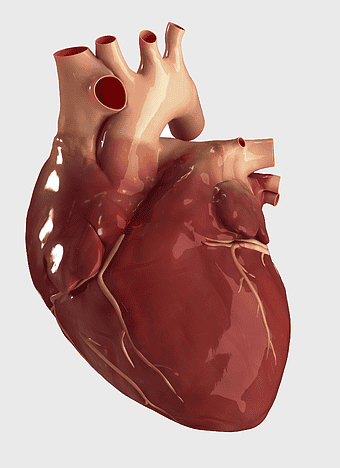

red heart anatomy, human heart drawing, cartoon heart illustration, love and biology, cardiovascular system diagram, medical art depiction, organ structure visualization -

heart bear illustration, myocardial infarction symptoms, cardiovascular disease diagram, red blood cell flow, heart anatomy art, circulatory system model, thrombus medical image -

human heart diagram, cardiovascular system anatomy, blood vessel chart, free body diagram, circulatory system illustration, medical organ visualization, human anatomy study -

human heart anatomy, cardiac muscle illustration, circulatory system model, heart health visual, cardiovascular organ diagram, medical heart image, visceral structure depiction -

heart anatomy illustration, cardiovascular system diagram, circulatory system medical, vascular system sonography, human body blood flow, arterial network visualization, heart function analysis -

human heart illustration, cardiac anatomy diagram, heart blood vessels, medical organ visuals, cardiovascular system chart, human anatomy study, circulatory system illustration -

Heart Anatomy Atrium, Aortic arch Human body, human circulatory system, ventricle and heart阀, cardiovascular health, thoracic cavity structures, heart valve functionality, atrium blood flow diagram -